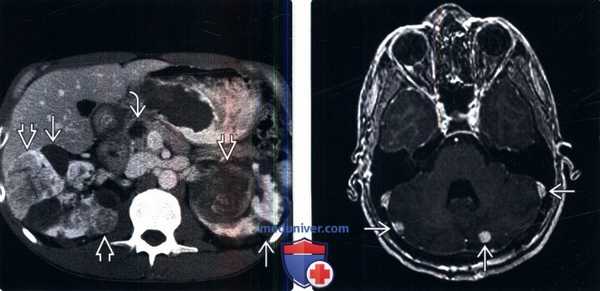

(Слева) КТ с контрастированием, аксиальная проекция: у пациента с болезнью Гиппеля-Линдау выявлены множественные двусторонние кисты почки и ПКР. Выявлено кистозное новообразование в головке поджелудочной железы. Поджелудочные проявления болезни Гиппеля-Линдау включают кисты, кистозные новообразования (микрокистозная аденома) и нейроэндокринные опухоли.

(Справа) МРТ, постконтрастное Т1-ВИ, аксиальная проекция: выявлены множественные контрастируемые патологические изменения мозжечка, что позволяет предположить гемангиобластомы.

Лучевые методы. На МРТ-изображениях головного мозга выявлено характерное двустороннее поражение глаз (рис. 1), по данным КТ — с участками обызвествления (рис. 2). Также на КТ головного мозга были выявлены зона послеоперационных кистозно-глиозных изменений с наличием кисты и узла на уровне посттрепанационного дефекта в правом полушарии мозжечка, а также аналогичные зоны дорзальнее и в субкортикальных отделах; в левой гемисфере мозжечка определялись кистозные изменения (рис. 3).

Рис. 1. Пациентка П., 30 лет, с диагнозом «Болезнь Гиппеля−Линдау»: магнитно-резонансная томография головного мозга

Примечание. А, Б — Т2- и Т1-взвешенные изображения. В полости правой глазницы объемное образование с неоднородным МР-сигналом; В — постконтрастное Т1-взвешенное изображение, режим подавления сигнала от жира: определяется интенсивное, но гетерогенное контрастирование образования. Кровоизлияние в сетчатку справа.

Рис. 2. Пациентка П., 30 лет, с диагнозом «Болезнь Гиппеля−Линдау»: компьютерная томография головного мозга

Примечание. Отмечаются гиперденсные зоны в области сетчатки и глазных яблок справа плотностью до +270…+330 HU.

Рис. 3. Пациентка П., 30 лет, с диагнозом «Болезнь Гиппеля−Линдау»: магнитно-резонансная томография головного мозга

Примечание. А — Tirm-режим: на фоне кист мозжечка визуализируется мягкотканный компонент, прилегающий к кисте справа; Б — DWI-режим: зона рестрикции диффузии по ходу стенки кисты справа; В — постконтрастное Т1-взвешенное изображение, режим подавления сигнала от жира: в той же зоне отмечается накопление.

При ультразвуковом исследовании поджелудочной железы эхографическая картина неотчетлива, по данным КТ паренхима поджелудочной железы диффузно изменена за счет множественных тонкостенных кист, вирсунгов проток не прослеживается (рис. 7).

Рис. 7. Пациентка П., 30 лет, с диагнозом «Болезнь Гиппеля−Линдау»: компьютерная томография поджелудочной железы

Примечание. А — нативная фаза: множественные тонкостенные кисты поджелудочной железы; Б — артериальная фаза: кисты визуализируются более отчетливо на фоне контрастированной окружающей ткани железы, но при этом участков патологического накопления поджелудочной железой нет.